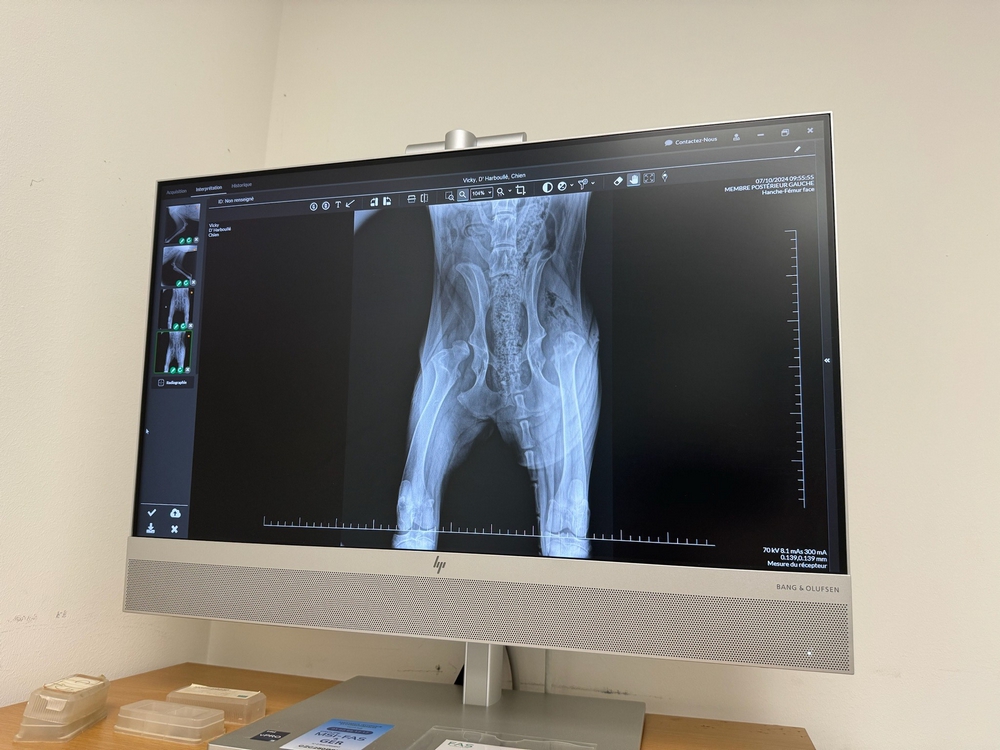

Notre clinique est équipé d’un échographe et d’une radiographie numérique ( système capteur plan et assistance à l’interprétation par IA ) .

La radiographie vétérinaire est une technique d’imagerie médicale qui permet de visualiser les os, les organes internes, les tissus mous et toutes les structures internes du corps des animaux. Les radiographies vétérinaires sont couramment utilisées pour diagnostiquer des fractures, des maladies pulmonaires, des problèmes cardiaques, des obstructions intestinales, des tumeurs, et bien d’autres affections.

C’est un outil précieux pour notre équipe vétérinaire afin d’établir un diagnostic précis, et planifier un traitement adapté pour vos chiens, chats et Nacs.